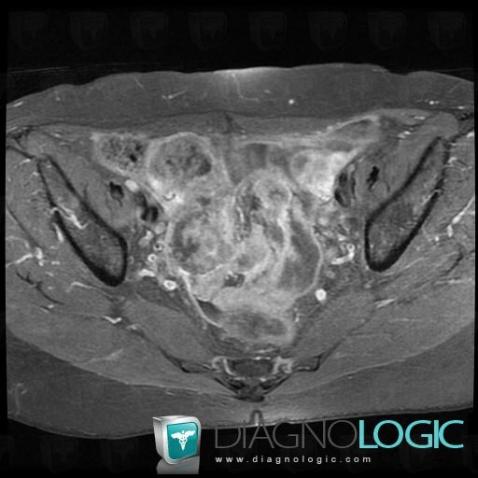

Serous cysteadenocarcinoma, Adnexa / Ovary fallopian tube, Pelvis / Perineum, MRI

Here is the specific information in the key image above:

- Diagnosis Serous cysteadenocarcinoma, Location(s) Adnexa / Ovary fallopian tube, with gamuts Solid adnexal massPelvis / Perineum, with gamuts Solid pelvic mass

- Diagnosis Serous cysteadenocarcinoma (link to Serous ovarian tumor), Location(s) Adnexa / Ovary fallopian tube, with gamuts T2 WI hyperintense adnexal mass